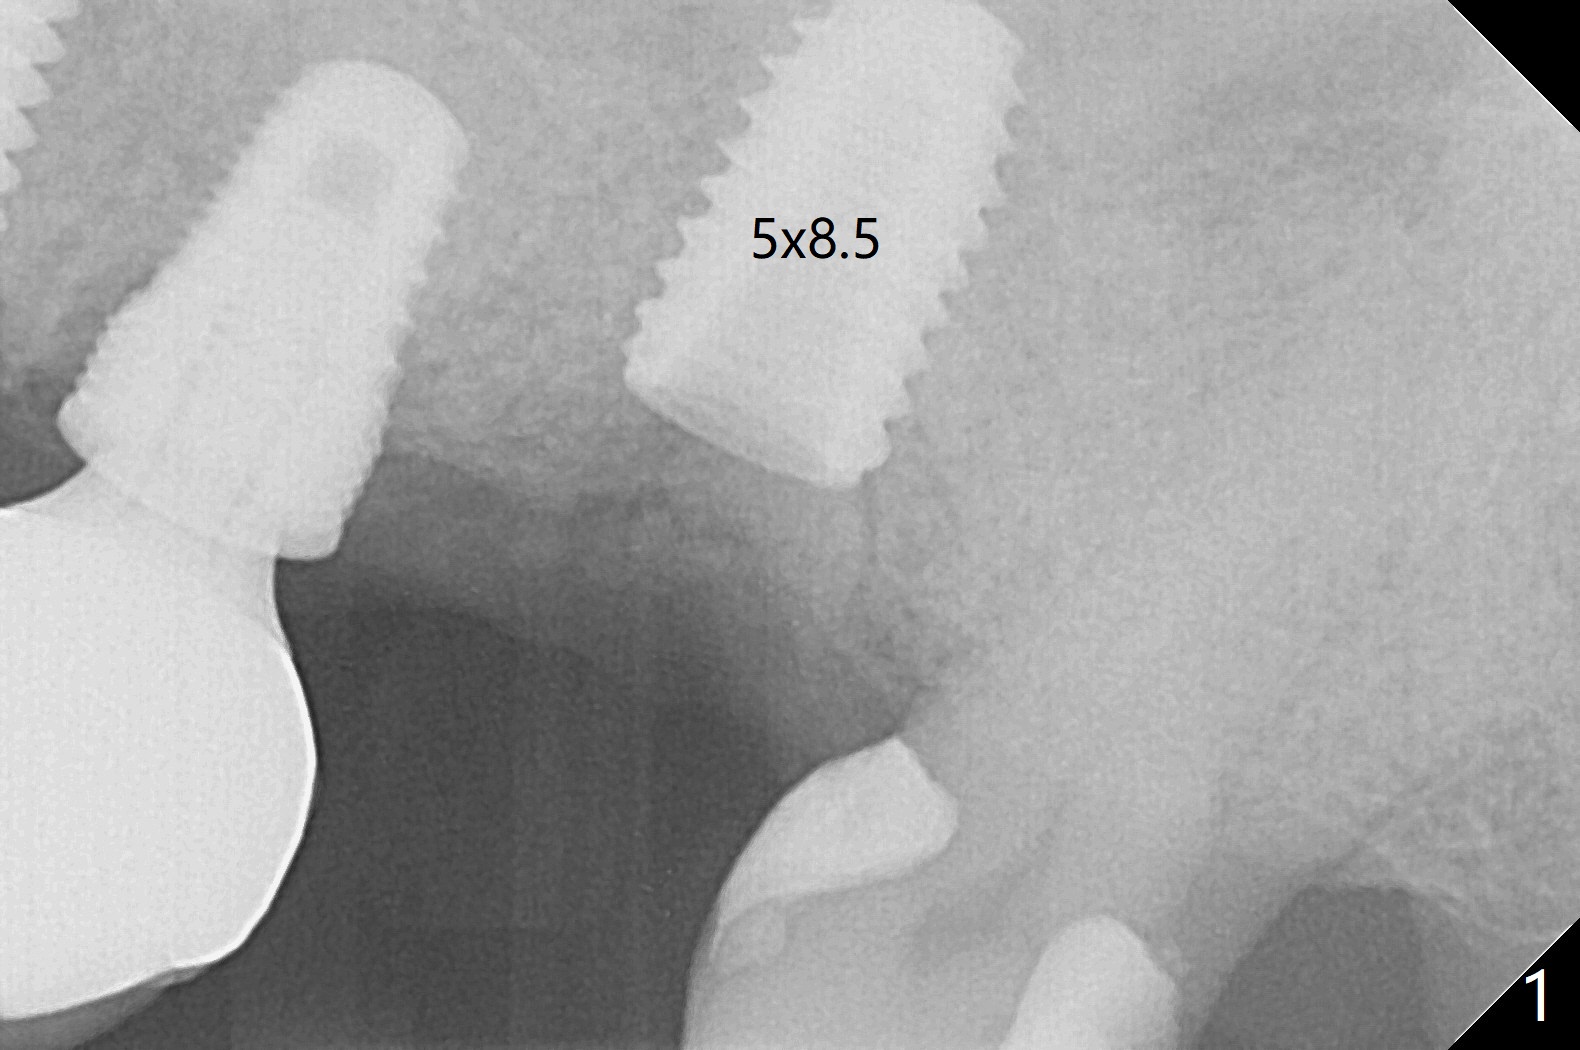

Due to low bone density post large implant (7 mm in diameter) removal with bone graft at #15, osteotomy with guide is underprep (last drill: 3.5x10 vs. 4.5x10 mm (design)). When a 4.5x10 mm dummy implant is placed at the beginning of the 1st line (10.5 mm offset), the torque is ~ 15 Ncm. As a 5x8.5 mm final implant is being placed, the torque increases to 30 Ncm (Fig.1,2) with apparently incidental sinus lift (Fig.3 arrows). The implant remains in place with a healing abutment 2 months 9 days postop (Fig.4). Healing abutment is changed from 5.5x6 to 6.8x5 mm 4.5 months postop when #16 MO composite is redo. There is bone loss at #14 mesially (Fig.5 *) with microthread exposure (<) less than 7 months before loosening.